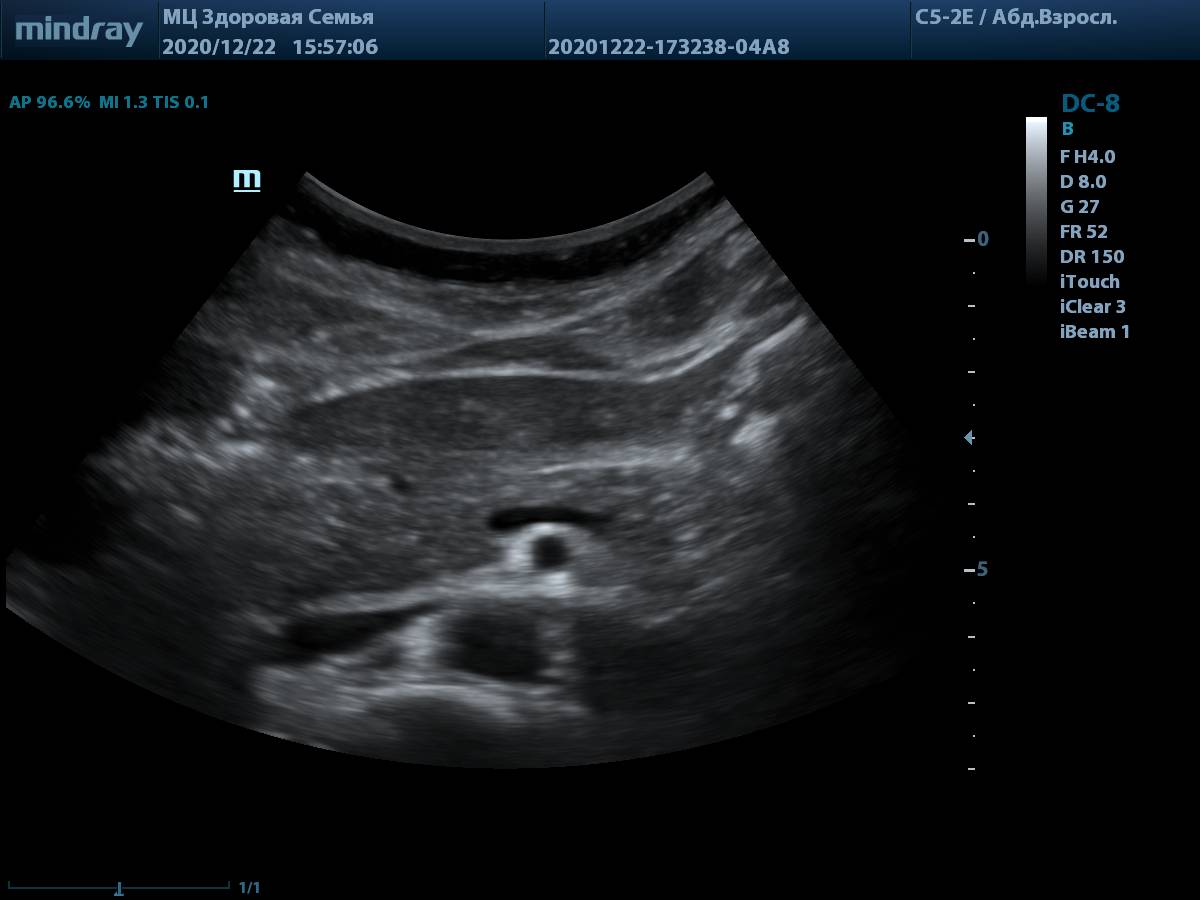

4. Пример визуализации поджелудочной железы у пациента с избытком массы тела, проблем с измерением органа и оценки его структуры нет. В качестве линзы использована левая доля печени.